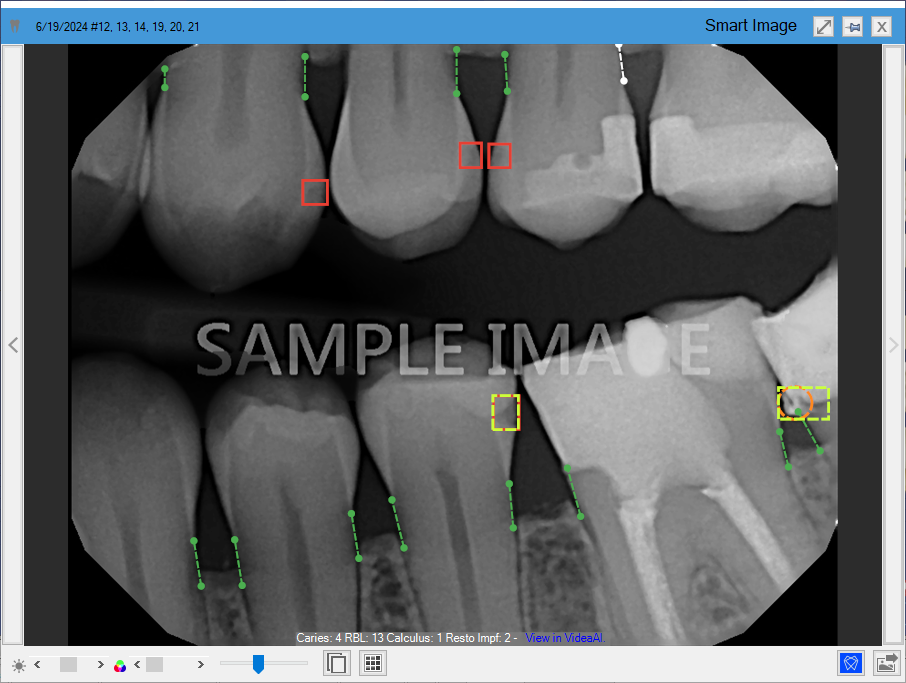

Detecting caries in the enamel (dotted line yellow rectangles) and dentin (solid line red rectangles) on all primary and secondary teeth of patients three years and older. This eliminates the need for manual analysis of all primary and secondary teeth, saving you and your hygienists time.

Measuring interproximal Radiographic Bone Levels in bitewings and Periapical Radiographs (PAs) for patients who are at least 12 years old. Bone level detection is only possible with mesial and distal surfaces. RBL measurements appear as green, yellow, orange, or red dotted lines.

Detecting interproximal calculus to educate your patients 12 years and older on the importance of scaling and root planing. Combined with measuring interproximal Radiographic Bone Levels, Dentrix Detect AI illustrates disease prognosis for the patient and clinician. Interproximal calculus is indicated by an orange circle or oval.

Detecting restoration imperfections in patients 22 years and older by identifying imperfect crown and filling margins and voids. A restoration imperfection is indicated by a yellow rectangle.

In Figure 1, caries are indicated by red squares, RBL is indicated by vertical dotted lines, calculus is indicated by an orange circle, and restorative imperfections are indicated by yellow rectangles.

Figure 1. Diagnostic Viewer with Dentrix Detect AI indications.